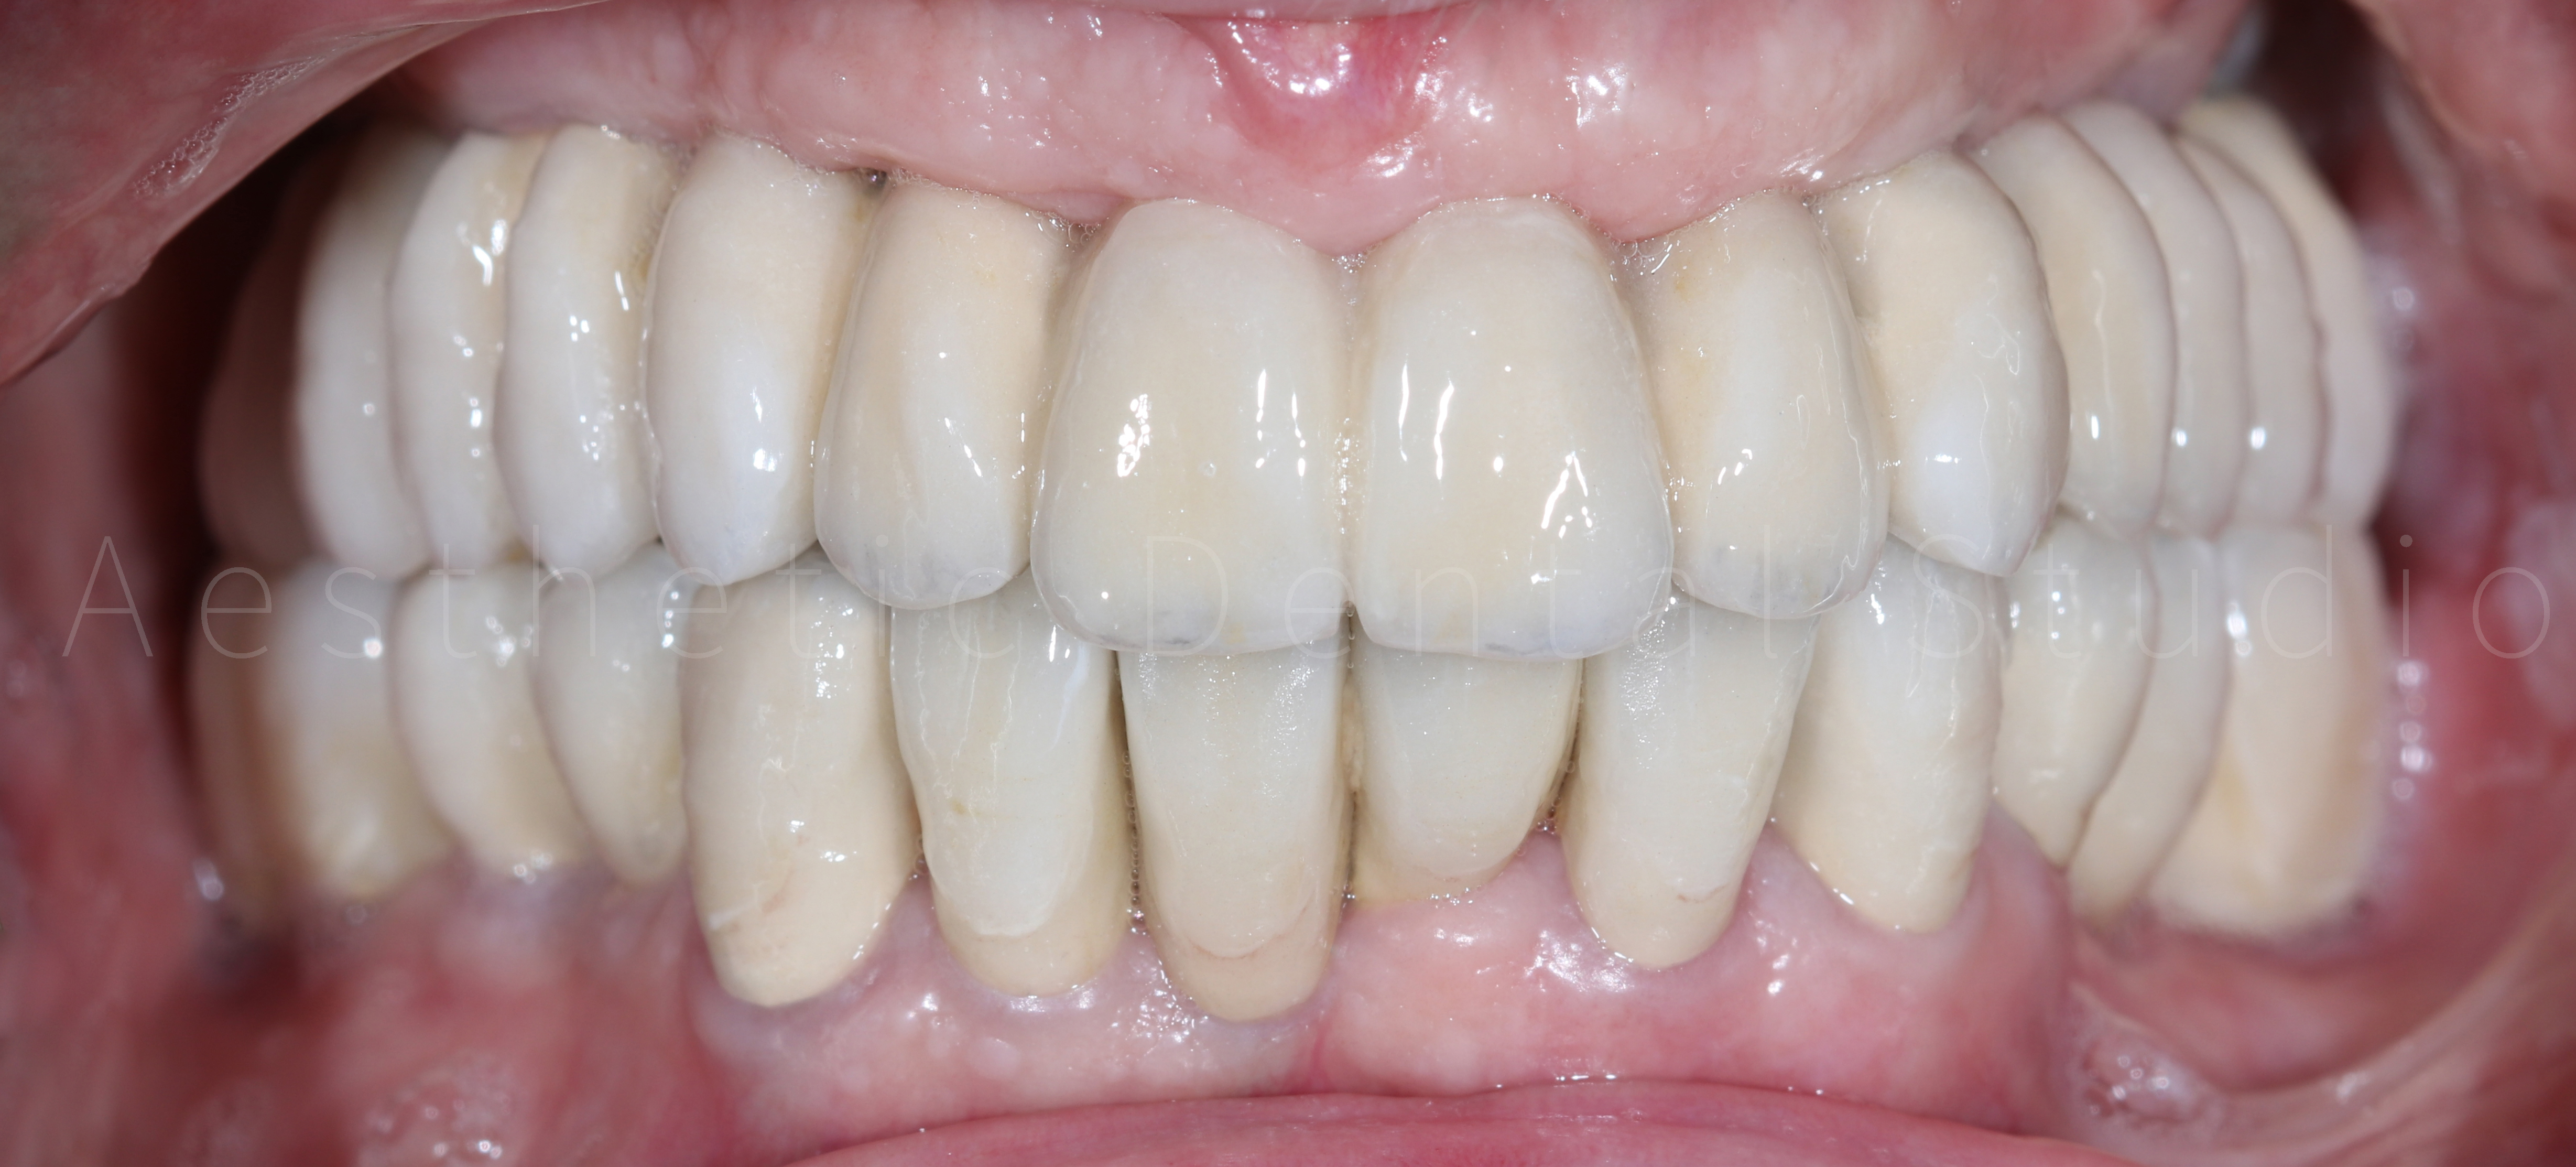

Αφού ολοκληρώθηκε η δοκιμαστική φάση και επιβεβαιώθηκε η άψογη λειτουργικότητα και αισθητική του σχεδίου, προχωρήσαμε στη λήψη ψηφιακών αποτυπωμάτων με ενδοστοματικό σαρωτή. Με βάση τα δεδομένα αυτά, σχεδιάστηκαν και τοποθετήθηκαν ακίνητες κεραμικές αποκαταστάσεις (στεφάνες και γέφυρες) πάνω σε δόντια και εμφυτεύματα, εξασφαλίζοντας απόλυτη ακρίβεια εφαρμογής και φυσικό αισθητικό αποτέλεσμα.

Το τελικό χαμόγελο της ασθενούς στο συνδύαζε αισθητική αρτιότητα, λειτουργική σταθερότητα και άνεση στη μάσηση και την ομιλία, προσφέροντας μια πλήρως ανανεωμένη στοματική εικόνα και αυτοπεποίθηση στην καθημερινότητά της.